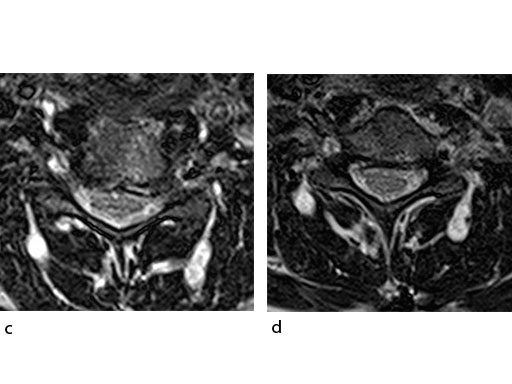

A 51-year-old woman was affected by cervical radiculo-myelopathy due to spinal and neuroforaminal stenosis. The preoperative CT scans are shown at Fig 4 and MRI at Fig 5.

The patient was treated by anterior cervical decompression and fusion (ACDF) with ZERO-P filled with ChronOS. No autologous bone graft was used. Postoperative images are shown (Fig 69).